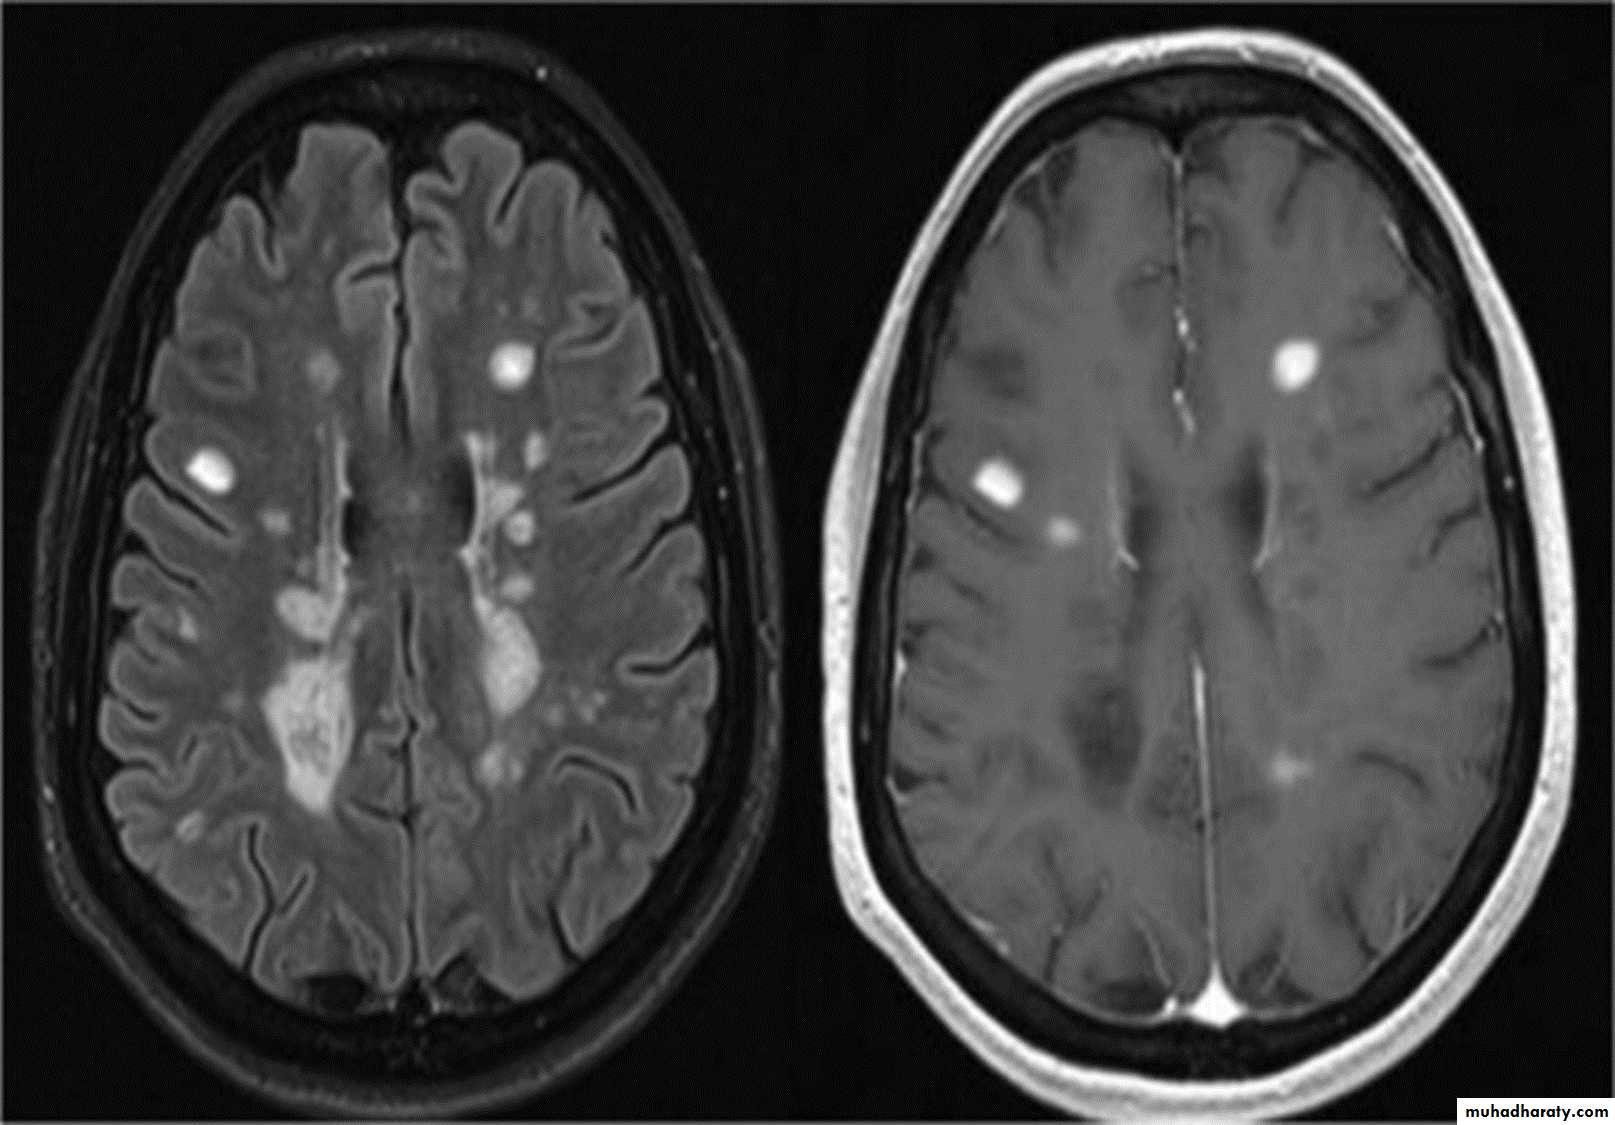

MRI :characteristic abnormalities are found in >95% of patients, although more than 90% of the lesions visualized by MRI are asymptomatic

Lesions are frequently oriented perpendicular to the ventricular surface,(Dawson’s fingers)

Lesions larger than 6 mm located in the corpus callosum, periventricular white matter, brainstem, cerebellum, or spinal cord are particularly helpful diagnostically

MRI shows multiple high-signal areas in a pattern similar to that of MS, although often with large confluent areas of abnormality. The CSF may be normal or show an increase in protein and lymphocytes (usually 200 cells/L) . The clinical picture may be very similar to a first relapse of MS.